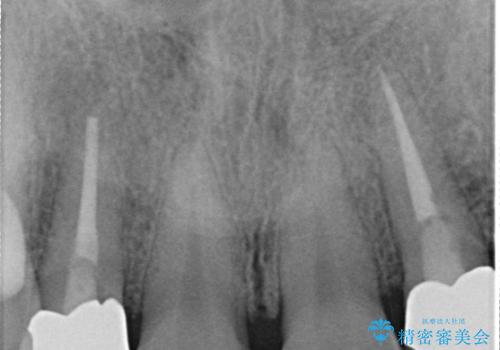

2日前に詰め物が取れ来院されました。中で虫歯が広がっている状態でした。歯科の治療が少し怖いとのことで静脈内鎮静を希望されました。

- 242,000円(仮歯1.1万円+オールセラミッククラウン15.4万円+静脈内鎮静7.7万円)費用は治療当時の料金となります

治療回数を減らしたかったため、虫歯をとり形成を行い仮歯への置き換えとともに型どりを行いました。